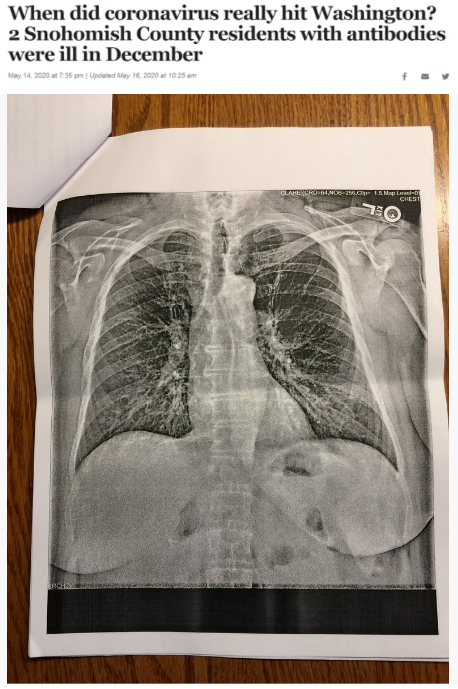

據《西雅圖時報》去年5月14日報道,華盛頓州斯諾霍米什縣的兩位居民在2019年12月出現類似新冠肺炎的癥狀,之后對他們的新冠病毒抗體檢測呈陽性反應。這一結果表明,新冠病毒可能比想象中更早在當地出現。

△《西雅圖時報》報道截圖(題圖中的X光片顯示其中一位斯諾霍米什縣居民的肺部“過度充氣”并出現“線性混濁”。醫生認為,這可能是疊加上呼吸道肺部感染的表現。)